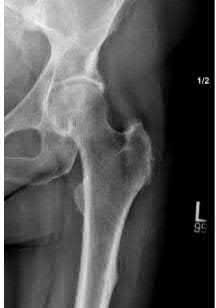

Question 2:

A 28-year-old male sustains a severe hyper-dorsiflexion injury to his ankle in a motor vehicle accident, resulting in a Hawkins Type III talar neck fracture. Which of the following arteries provides the predominant blood supply to the body of the talus, placing it at significant risk for avascular necrosis in this injury?

Correct Answer: Artery of the tarsal canal

Explanation:

The artery of the tarsal canal, which is a branch of the posterior tibial artery, provides the dominant blood supply to the talar body. In a Hawkins Type III fracture (talar neck fracture with subtalar and tibiotalar dislocation), the blood supply from the artery of the tarsal canal, the artery of the sinus tarsi, and capsular vessels are disrupted, leading to an avascular necrosis (AVN) rate approaching 100%.